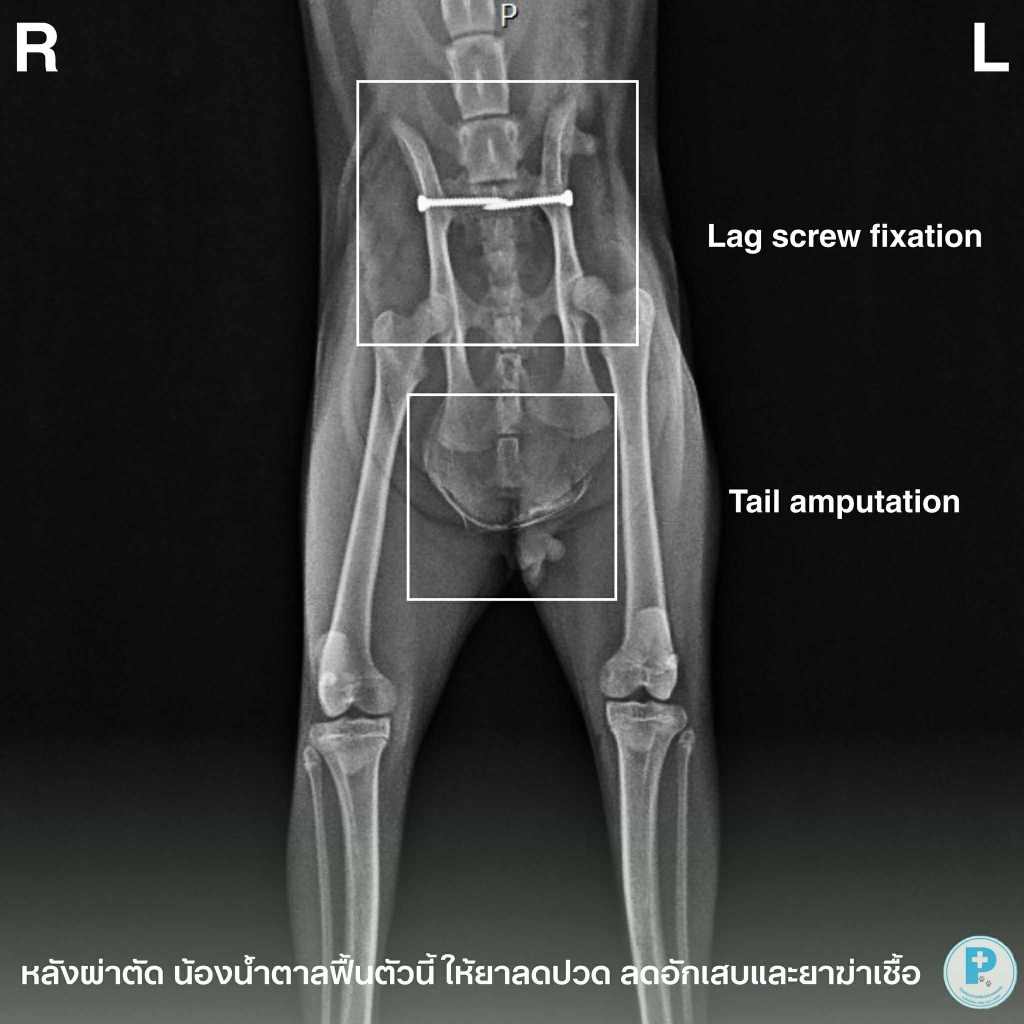

- แมวโดนรถชน กระดูกหัก

น้อง มาบิว มาด้วยประวัติถูกรถชน ตรวจ X-ray พบว่า

Both sacroiliac luxation ร่วมกับ pubis fracture

(ข้อเชิงกรานทั้งสองข้างเคลื่อน + กระดูกหัวหน่าวหัก)

ซึ่งเป็นภาวะที่ทำให้เชิงกราน “เปิดออก” ถ้าไม่ผ่าตัด น้องจะเสี่ยง เดินไม่ได้ถาวร / ปวดเรื้อรัง / อวัยวะในอุ้งเชิงกรานเสียหาย

แนวทางการรักษาทำการผ่าตัด Both SI lag screw fixation

เพื่อจัดแนวเชิงกรานกลับสู่ตำแหน่งปกติและยึดให้มั่นคง

ภาพ X-rayภาพก่อนผ่าตัด : เห็นข้อ SI ทั้งสองข้างเคลื่อน + pubis fracture

ภาพหลังผ่าตัด : เชิงกรานกลับเข้าที่ ล็อกด้วย lag screw อย่างมั่นคง

เป้าหมายการรักษา

ลดอาการปวด

ป้องกันความพิการถาวร

ให้น้องกลับมาเดิน ใช้ชีวิตได้ใกล้เคียงปกติที่สุดผ่าตัด: สพ.ญ.ณัฐฐ์ธวรรณ โสภิพันธ์ (หมอพลอย)

เรียบเรียง: น.สพ.นรภัทร โสภิพันธ์ (หมอพีท)